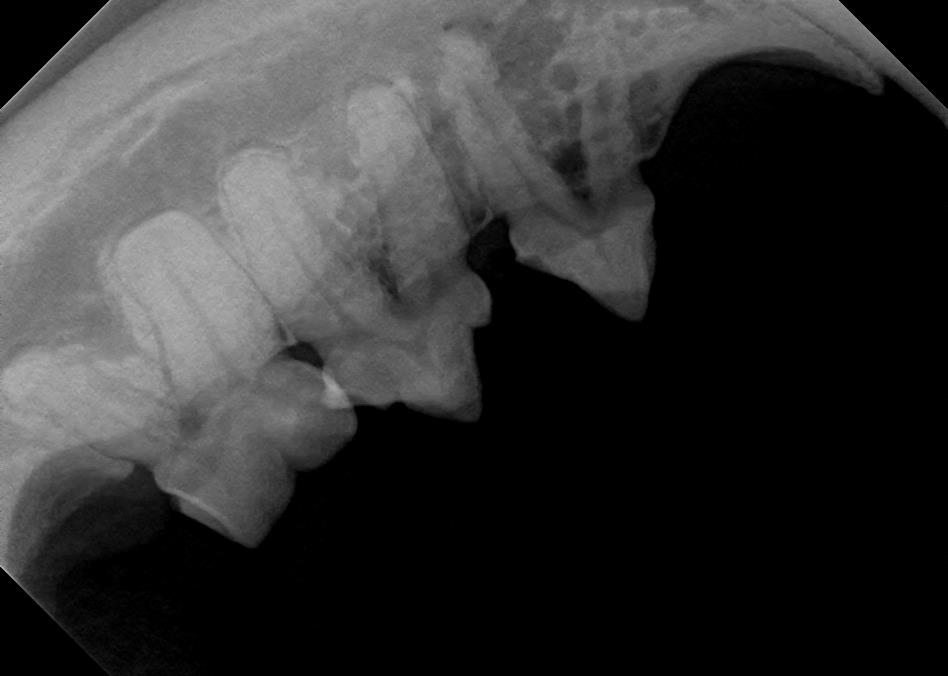

Examples of healthy teeth:

At A Couple of Vets, our animal hospital staff is well-versed in the latest dental cleaning techniques to remove plaque and tarter from the teeth’s surface as well as from below the gum line. We perform dental x-rays at every cleaning to ensure that the teeth are completely healthy. They may look good on the surface, but many problems occur below the gum line and are only visible with x-rays.